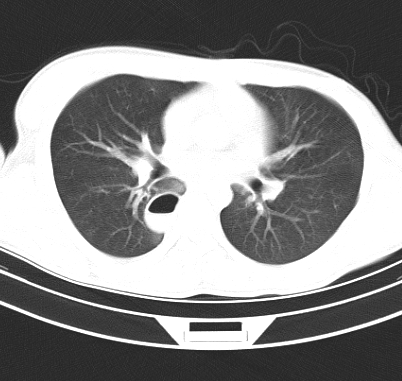

标题: CT19170:男 24岁,胸部外伤一周行CT检查 [打印本页]

男 24岁,胸部外伤一周行ct检查 未传纵隔窗

结合病史考虑肺挫伤后所致的肺气囊表现

结合临床考虑为右肺下叶背段撕裂伤。

首先考虑肺裂伤形成的液气囊肿.纵膈胸膜包裹性的液气胸可能性小,病变主要在肺内.

支持外伤性肺气囊。